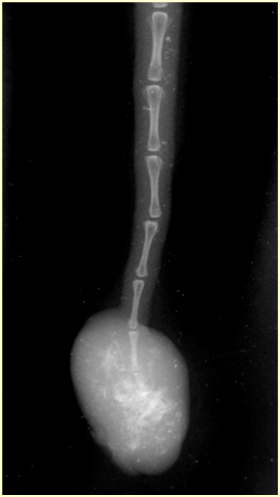

尾部に発生する脊索腫は、典型的には飼い主が尾の先端に気付く硬い腫瘤として発見されます 。この腫瘤は通常、滑らかで被毛がなく、成長が緩徐であり、触診時に痛みを伴わないことが多いです。 腫瘍の肉眼的な特徴として、灰白色で膨張性を持つ皮下軟部組織塊として観察されます 。全身状態は良好であることが多く、腫瘍が尾の先端にあるため、地面に擦れることによって、表面に潰瘍を形成したり、被毛が抜けたりする付随的な問題は生じますが、それ自体が動物の生活に深刻な影響を与えることは稀です〔Williams et al.1993〕 。

画像診断は、腫瘍の局所的な広がり、骨組織への浸潤、および脊髄への影響を評価するために必須です。X線検査では尾部病変の場合、腫瘤の大きさや、尾椎における骨の破壊(溶骨性変化)の有無を確認します。 MRIおよびCT検査では、脊椎病変の場合、腫瘍が脊髄を圧迫している程度を評価することが治療方針の決定に不可欠であり、MRIが最も正確で詳細な情報を提供します 。MRIは、腫瘍の周囲軟部組織への浸潤範囲や、脊髄の圧迫度を評価する上で、ミエログラフィーよりも正確であるとされています 。CTも外科的切除の可能性を判断する上で有用な画像技術です 。